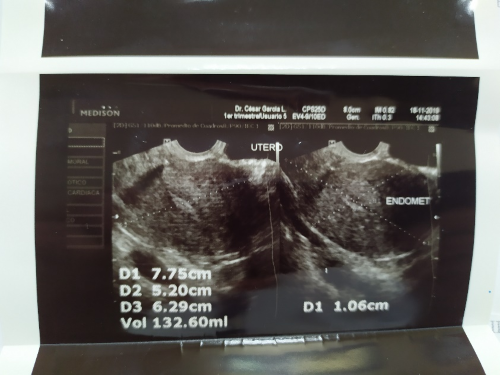

Se indican estudios de laboratorio: ante la sospecha clínica de embarazo se solicita β-HCG cualitativa la cual resulta positiva y cuantitativa que reporta resultado de 323 UI/L, grupo sanguíneo O Rh (+). Se realiza ecografía transvaginal (Figuras 1,1; 1,2; 1,3) que reporta útero en anteversión de contornos regulares, diámetros 7,7 x 5,2 x 6,2cm con un volumen estimado de 132cc, la ecogenicidad de su miometrio está afectada por una lesión hiperecogénica en relación a mioma que mide 1,9 cm en pared anterior, ovario derecho aumentado de volumen doloroso a la exploración de 4,2 x 2,2cm con imagen de pseudo saco con líquido en su interior y una imagen folicular de 1 cm en el mismo anexo, ovario izquierdo normal, espacio de Douglas luce libre; lo cual sugiere embarazo ectópico accidentado de ovario derecho.